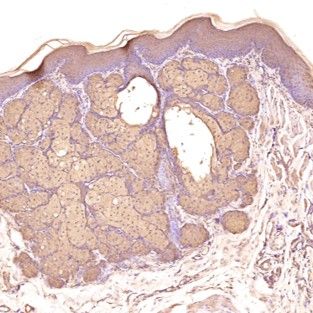

免疫組化染色-卵巢

IHC免疫組化

856